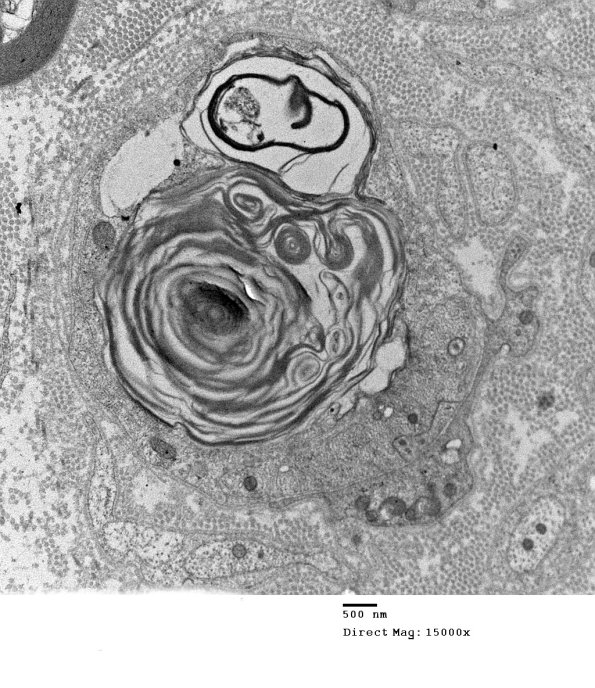

The residua of axonal degeneration consists of myelin debris held within a Schwann cell. (electron micrograph)